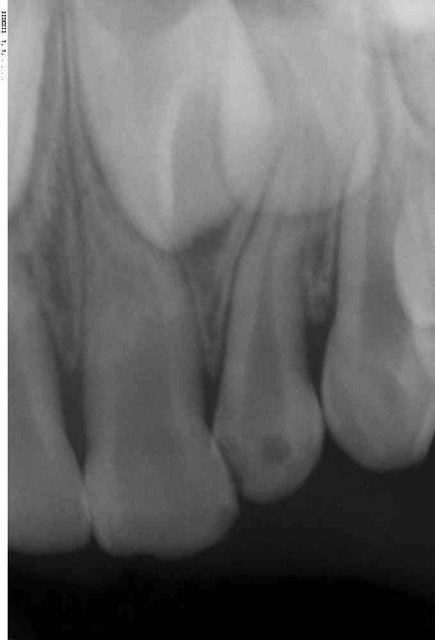

j'ai reçu une petite de 4 ans d'origine asiatique ( pigmentation). Elle est tombée il y a 15j, ses parents l'ont amenée aux urgences pédiatriques à l’hôpital car elle avait un gros œdème a la lèvre

aujourd’hui présence d'un liserer rouge au collet de 51 et 52 et au niveau des apex de ces mêmes dents il y a une tuméfaction dure. Pas de douleur, elle mange normalement

mouvement de la 11, c'est effectivement ce que j'ai craint surtout vu son inclinaison. C'est pour cela que j'ai fait (et vous ai mis) une radio de 21 mais même inclinaison

nécrosée elle doit l'être vu sa couleur

pas de mobilité de 51 par contre c'est la perte d'attache au collet qui me stress